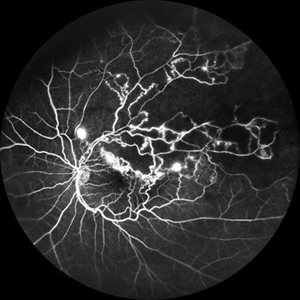

Branch Retinal Vein Occlusion

Jul 23 2025 by Malvika Singh

Fluorescein angiogram of a 52 year old man showing capillary non perfusion areas and leakages along the superotemporal arcade and at the macula.

Photographer: Dr Malvika Singh, Retina Foundation, Ahmedabad, India

Imaging device: Mirante SLO/OCT

Condition/keywords: branch retinal vein occlusion (BRVO), CNP areas, FLUORESCEIN ANGIOGRAPHY, fluorescein leakage, macular edema